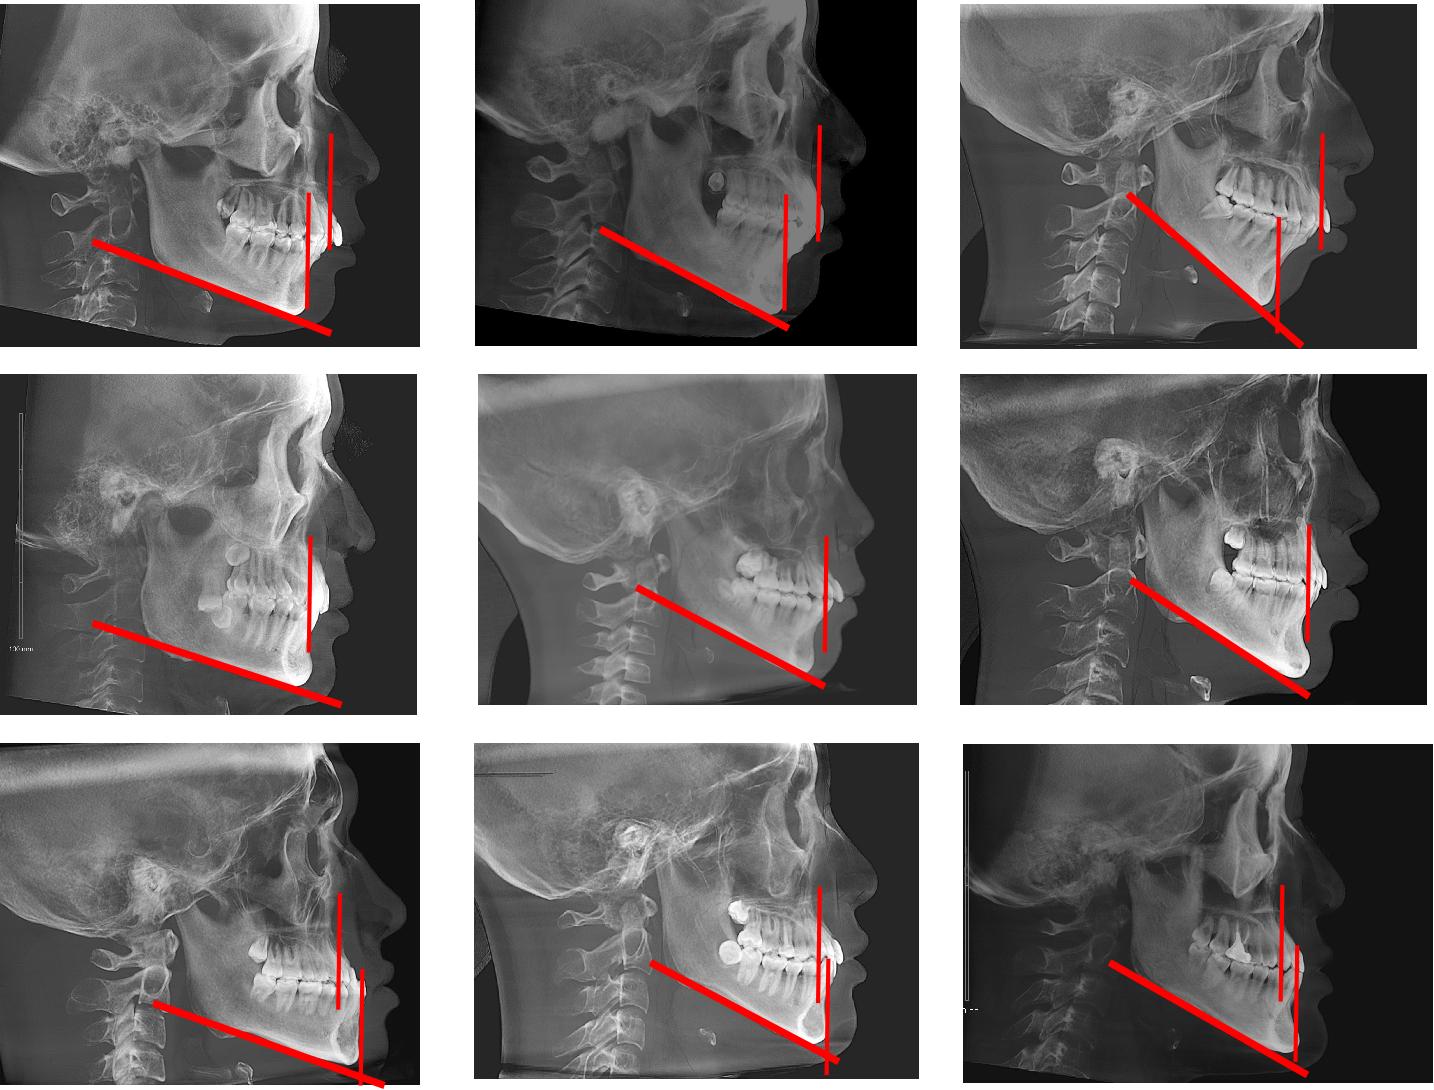

下颌骨垂直向有均角、低角、高角。

下颌骨前后向有前突(III类骨型)、后缩(II类骨型)、正常(I类骨型)。

二者相乘就会有九种情况:

第一行都是下颌后缩(骨型II类),第二行都是正常(骨型I类),第三行都是下颌前突(骨型III类)

第一列都是低角,第二列都是均角,第三列都是高角。